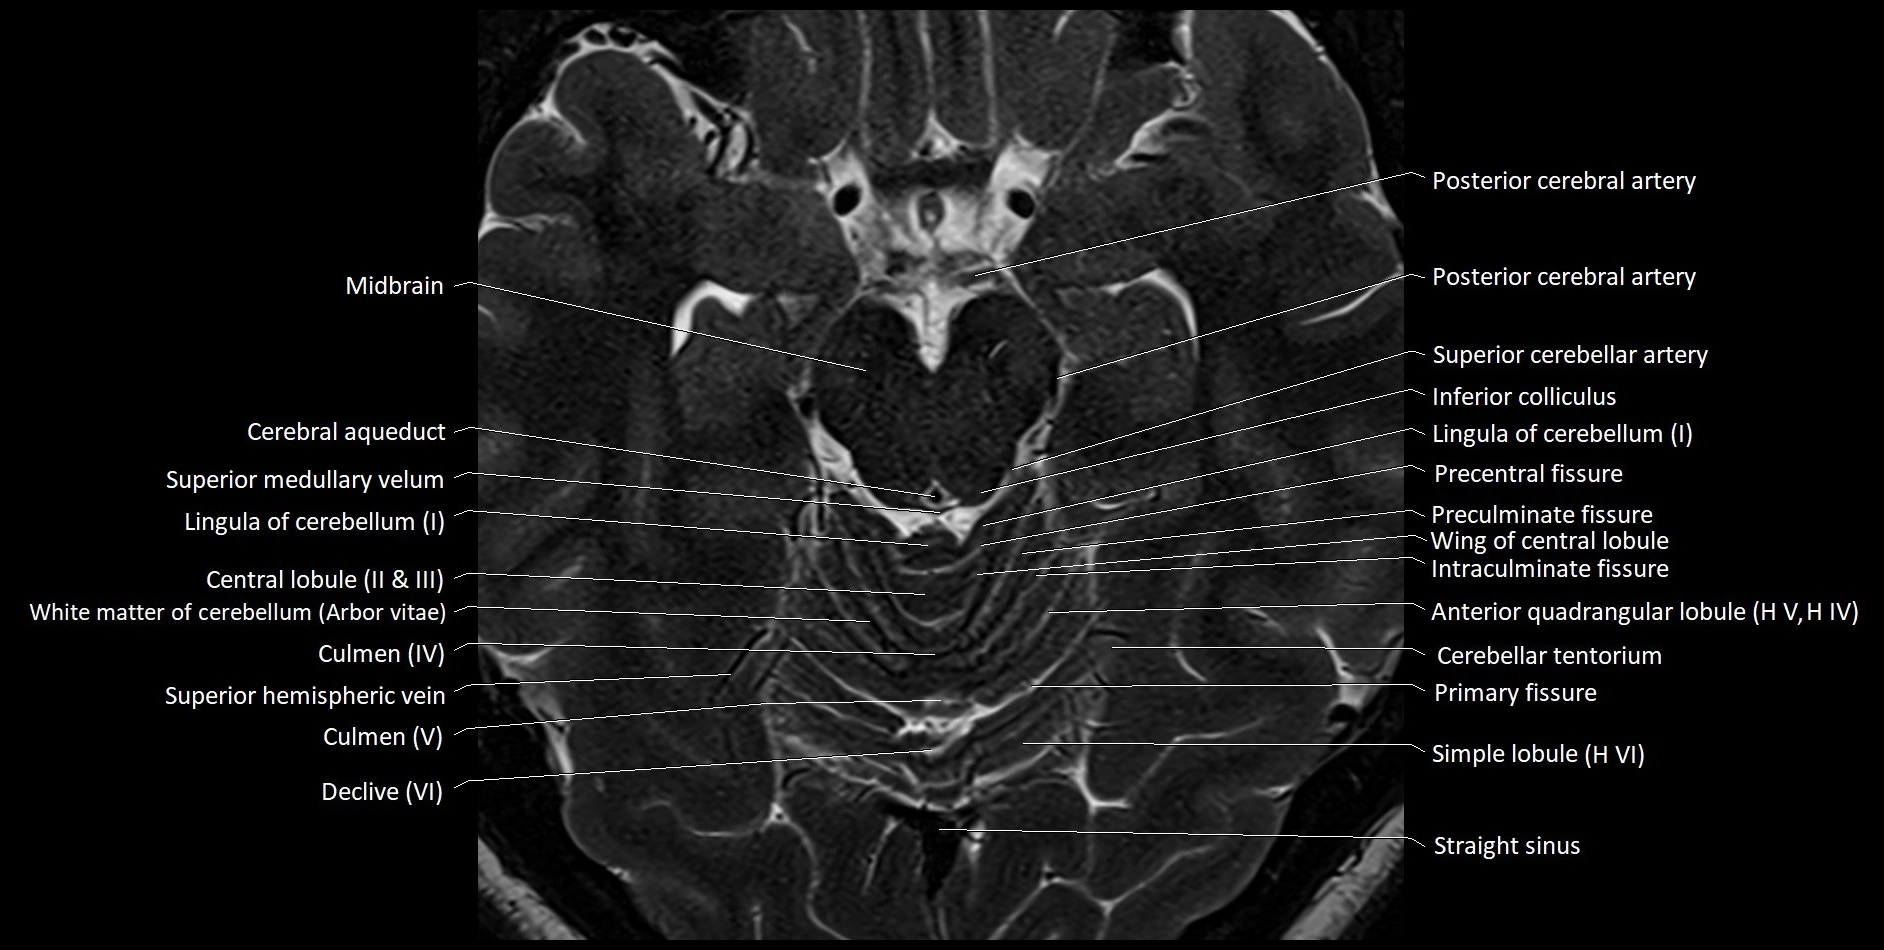

- Central lobule (II & III) of Cerebellum

- Culmen (IV, V) of Cerebellum

- Declive (VI) of Cerebellum

- Lingula of cerebellum (I)

- Precentral fissure

- Preculminate fissure

- Primary fissure

- Superior medullary velum

- Wing of central lobule